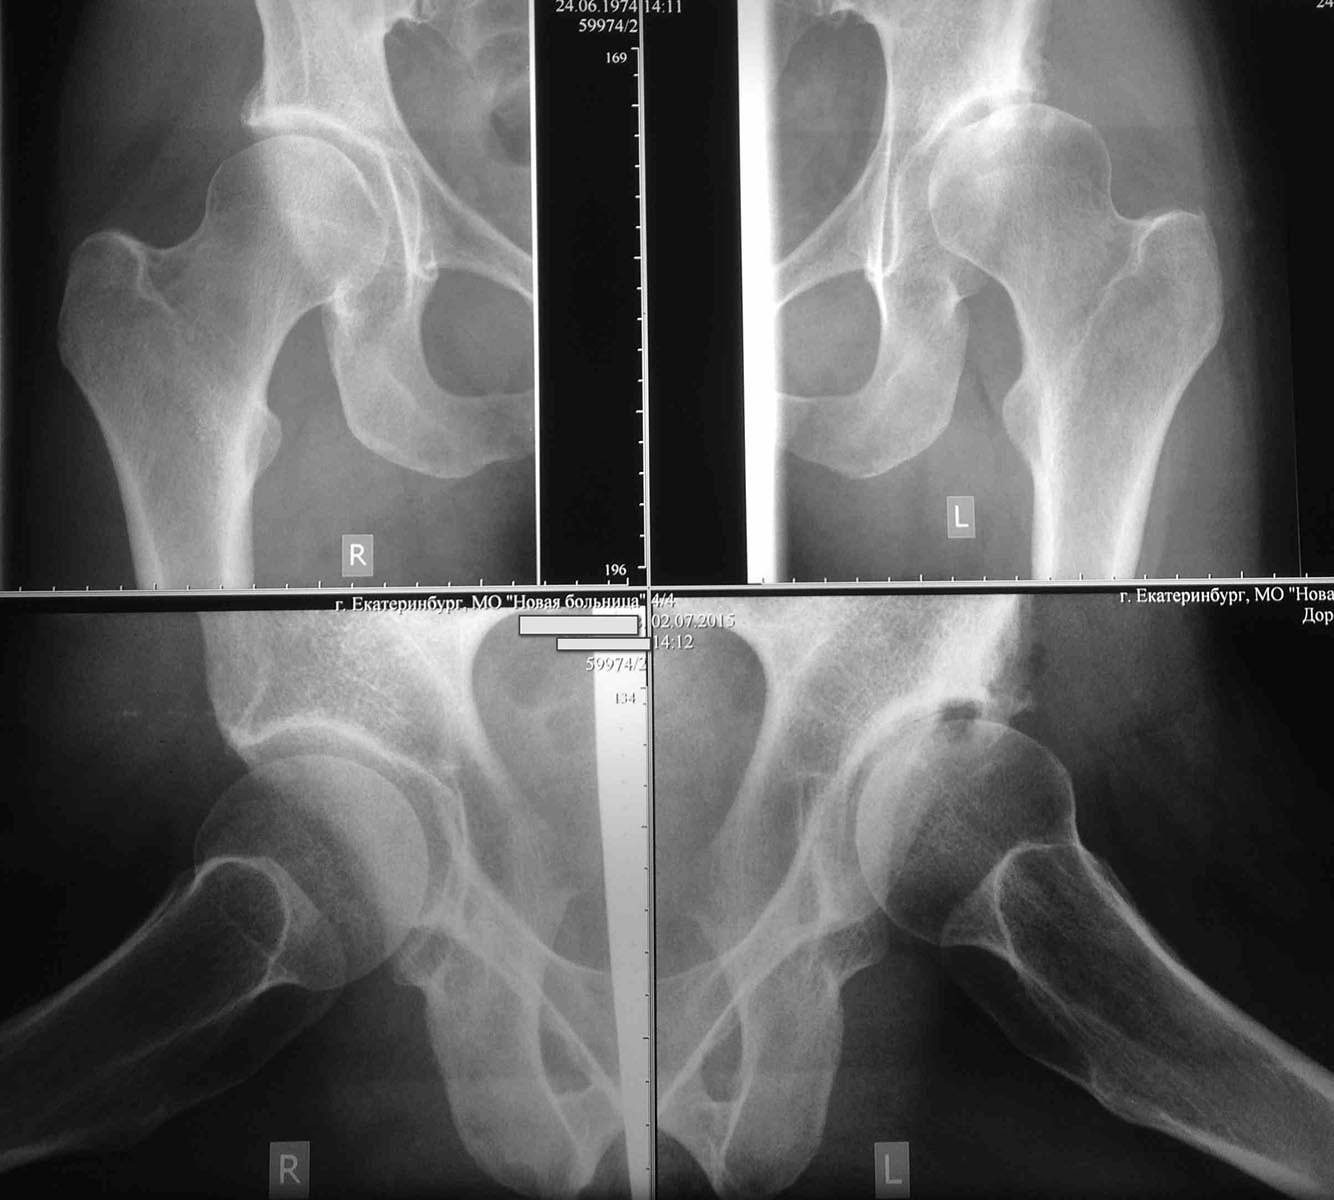

Обратилась молодая приятная женщина 41 года с диспластическим коксартрозом.

Беспокоит боль в левом тазобедренном суставе при движениях. Везде, где она консультировалась однозначно предлагали эндопротезирование. На мой взгляд за сустав еще можно побороться.

Максим, доброго Вам дня. Да, мы делаем эти операции все чаще и быстрее)), но в данном случае у меня есть сомнения, не поздно ли? Для того что бы развеять эти сомнения Б-й показана МРТ с измерением толщины хряща, если толщина менее 2-3 мм, то результат ПАО будет плохой и проще сделать ЭТБС

Другой простой и надежный вариант это выполнение рентгенографии наряду со стандартной прямой проекцией ТБС в прямой проекции с максимальным отведением бедра. Сужение щели в латеральном отделе на доп.проекции по сравнению со стандартной прямой проекцией ТБС также укажет на неблагоприятный прогноз.